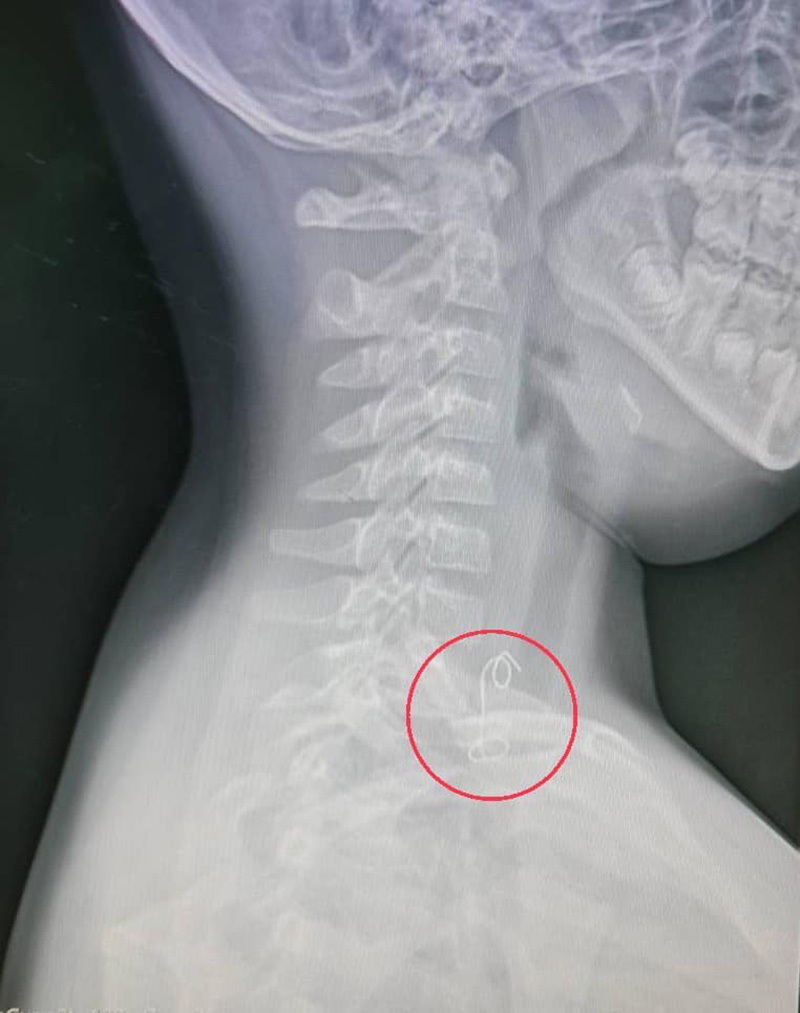

แพทย์ห้องฉุกเฉินส่งเอกซเรย์ เห็นเป็นวัตถุคล้ายขดขวดติดอยู่บริเวณส่วนต้นหลอดอาหาร ปรึกษาแพทย์ผู้เชี่ยวชาญด้านหู คอ จมูก เปิดห้องผ่าตัดด่วน ต้องดมยาสลบวิธีพิเศษใส่ท่อช่วยหายใจทางจมูกเพื่อป้องกันไม่ให้สำลักระหว่างผ่าตัด ใช้เครื่องมือส่องกล้องคีบเอาสิ่งแปลกปลอมออกมาได้ สิ่งที่เห็นนอกจากเศษปีกไก่ย่างที่ยังติดค้าง รวมไปถึงลวดมัดไก่ย่าง ยาวประมาณ 8 เซนติเมตร ออกมาด้วยได้สำเร็จ ผู้ป่วยพักฟื้นในโรงพยาบาลฉีดยาต้านเชื้อ 3 วัน ให้กลับบ้านได้อย่างปลอดภัย